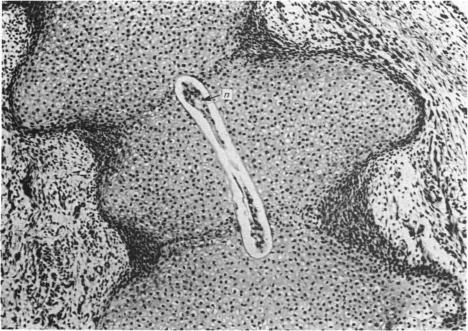

Bone formation in the vertebral centra commences within the centrum and is in this respect analogous to the secondary ossification which occurs in the epiphysis of a long bone. Bone tissue first appears at about the 85 mm C.R. stage and not in the 55 mm C.R. length embryo; at the latter stage blood vessels and calcification alone were observed. The connective tissue cells within the cartilage canal appear to assist osteogenesis by providing osteogenic cells which lay down bone in the walls of the cartilage canal, and provide cells which remove calcified cartilage found at the periphery of the canal; they assist growth by producing an appreciable number of chondrocytes that permit lateral expansion of the centra. Osteogenesis appears to occur in multiple foci within the growth plate of the older embryos and could account for the rapid rate of growth of vertebrae. Bone formation occurs in both mineralised and unmineralised matrix (as seen on the walls of the cartilage canals). The blood vessels within the growing vertebra tend to follow the zone of cartilage hypertrophy.